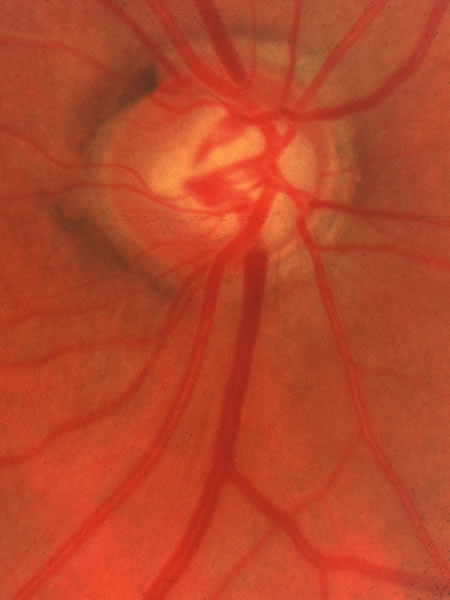

The approximately 1 to 1.5 million axons that form the optic nerve arise from the retinal ganglion cells and course toward the optic disc in a well-known pattern (Fig. 1). From the nasal retina the fibers take a straight course toward the disc. Axons originating temporal to the fovea arc around the macula to enter the upper and lower poles of the optic nerve head. The macula fibers pass directly to the temporal quadrant of the disc in the papillomacular bundle.

Fig. 1. Fundus photograph shows the normal pattern of the retinal nerve fiber layer. (Courtesy of P. Juhani Airaksinen, MD).